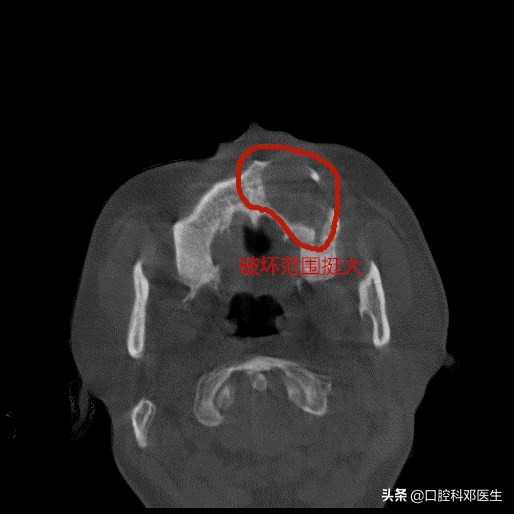

水平位片

囊肿波及范围大

接诊的邓医生介绍:这位患者脸肿大是由于左侧上颌骨内一个埋伏多生的牙齿所引起的,由于牙齿无法正常萌出,经过时间的积累,从而诱发囊肿,囊肿一般都不痛不痒,越长越大,像鼓气球一样,逐渐破坏了周围的骨头,如破坏上颌骨前壁,就会突破至软组织,引起脸部肿大;如破坏牙槽骨,则会导致牙齿松动移位,引起牙根吸收疼痛等症状。